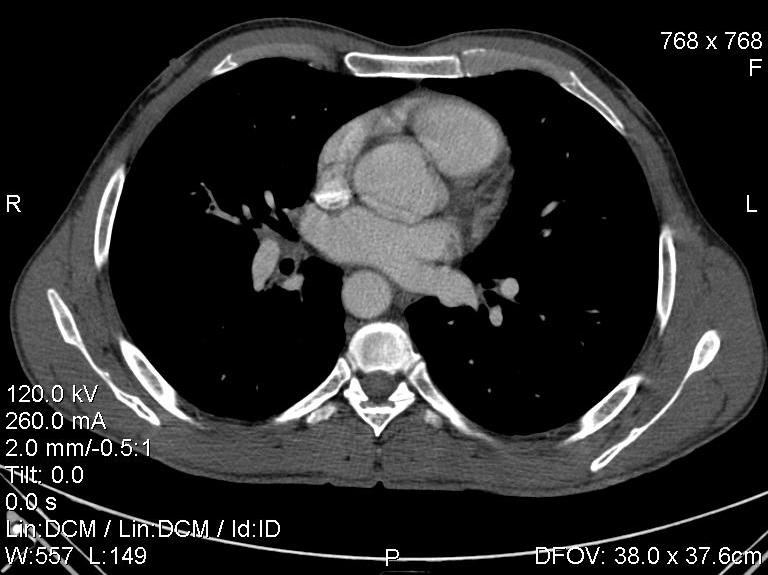

Пациент был направлен на КТ после рентгенографии ОГК, с направительным диагнозом: объёмное образование верхнего средостения.

это аномально расположенная грудная аорта

Конечно, дуга аорты идёт справа от позвоночника (декстра позиция); но есть и ещё одна аномалия той же группы: